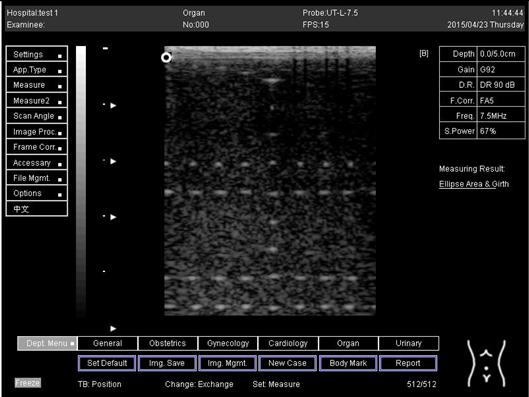

9.0 Axial resolution

Biomimetics 07 00130 i001

D1 = 4.9

D2 = 4.1

D3 = 3.1

D4 = 2.2

Lateral resolution

Biomimetics 07 00130 i002

D1 = 5.0

D2 = 4.0

D3 = 3.0